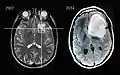

En début d'évolution, l'imagerie montre une tumeur isodense au scanner, d'où l'intérêt de l'IRM, plus sensible au dépistage de cette tumeur peu vascularisée. Lors de l'évolution, le scanner montre une tumeur hypodense, ne prenant généralement pas le produit de contraste. Il n'est pas retrouvé d'effet de masse puisque la tumeur est infiltrante.